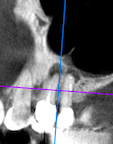

Santi Опубликовано 31 октября, 2023 Поделиться Опубликовано 31 октября, 2023 (изменено) Короткая нарезка с операции резекции 14-15. Апикально материал на основе минерал триоксид агрегата. Критике и комментам всегда рад. Изменено 31 октября, 2023 пользователем Santi 5 2 Ссылка на комментарий